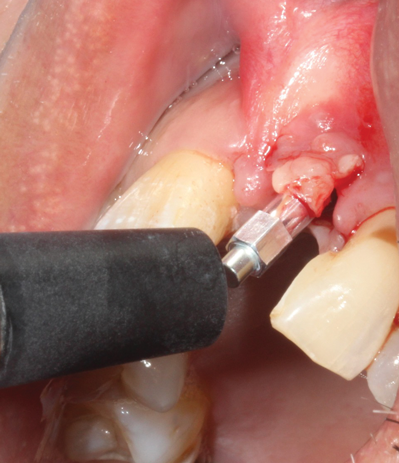

(35.) An implant being inserted into the prepared osteotomy of a patient who presented for the replacement of the maxillary left central incisor.

Figure 35